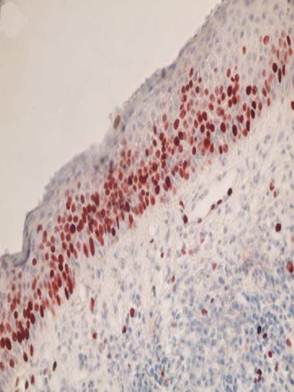

Most of the Ki- 67 cells being detected in the suprabasal layers (Figure 1) The AgNOR dots were higher in the nucleus of subrabasal cells than basal cells in KCOT (Figure 2).

Figure 1

Representative photomicrograph of keratocystic odontogenic tumor stained with Ki-67. Immunoreactivity was observed particularly in the suprabasal cell layers of lining epithelium. (x400)

Ki-67 antibodies are useful in establishing the cell growing fraction in neoplasms. Ki-67 expression has been shown to be higher in the epithelium of KCOTs when compared with developmental and inflammatory cysts, with most of the Ki- 67 cells being detected in the suprabasal layers, as reported in our study (2, 3, 29).